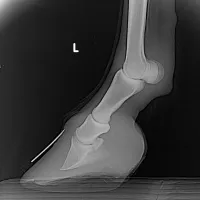

HUFREHE

Die Hufrehe ist eine schmerzhafte und potenziell lebensbedrohliche Erkrankung bei Pferden, die die Hufe betrifft. Hier sind einige wichtige Informationen dazu:

Was ist Hufrehe?

Es handelt sich um eine Entzündung der Huflederhaut, die das Hufbein mit der Hornkapsel verbindet.Diese Entzündung kann zu einer Ablösung des Hufbeins von der Hornkapsel führen, was extreme Schmerzen verursacht und im schlimmsten Fall zum Ausschuhen führen kann.